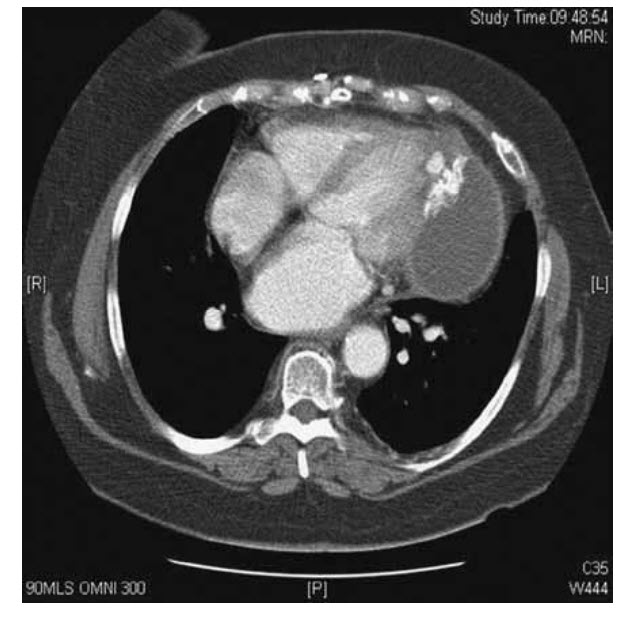

You are asked to see a 67-year-old male who presents with chest pain and a chronic non-productive cough. The symptoms had been present for over 8 months and were not progressing. He denied any haemoptysis. He had no significant past medical history. Cardiovascular and respiratory examination was unremarkable. Routine blood tests were normal. A CT chest is shown in Figure below

Congenital pericardial cysts are relatively frequent. They may be uni- or multilocular of diameter 1–15 cm and are full of serous fluid. Although most patients are asymptomatic, cysts may also present with chest pain, dyspnoea, palpitations, or cough. Although echocardiography is useful, additional imaging by CT or CMR is often needed. The treatment for symptomatic congenital cysts is percutaneous aspiration and ethanol sclerosis. If this is not feasible, video-assisted thoracotomy or surgical resection may be necessary. Guidelines on the diagnosis and management of pericardial diseases: Executive Summary. Eur Heart J, 2004; 25: 587–610.